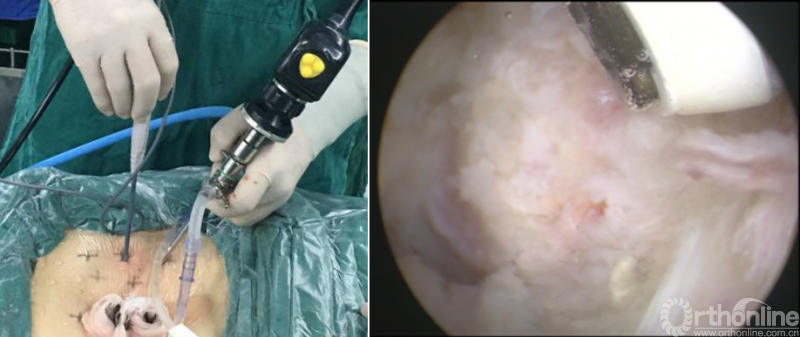

第七步“牵”:神经拉钩牵拉保护神经根;

第八步“铰”:铰刀置入处理上下终板(刮勺置入处理终板);

第九步“填”:椎间隙填塞植骨;

第十步“置”:置入融合器、经皮钉。

病例分享:(滑动查看)